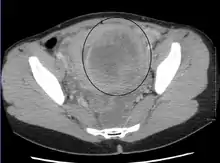

Multiple uterine leiomyoma

Large subserosal fibroid

Multiple uterine leiomyoma with calcification

Fibroids are monoclonal tumors and approximately 40–50% show karyotypically detectable chromosomal abnormalities. When multiple fibroids are present they frequently have unrelated genetic defects. Specific mutations of the MED12 protein have been noted in 70 percent of fibroids.[29]